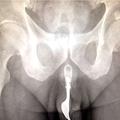

Na urgenci zdravniki vidijo vse mogoče in tako je nastal tudi letošnji seznam predmetov, najdenih v vaginah in penisih, ki ga ponuja baza podatkov ameriške komisije za varnost potrošniških izdelkov.

Nekateri so jo odnesli brez posledic, nemalo jih je pristalo tudi v bolnišnicah, od koder tudi izvira seznam. In da ne bo pomote, večina od teh predmetov, v te majhne človeške odprtine ni zašla pomotoma.  Pri večini je šlo za izvajanje spolne prakse, pri kateri nekateri pač doživljajo vzburjenost ob tlačenju določenih predmetov.

Na seznamu žensk, ki so potrebovale kirurško pomoč, najdemo predmete kot so kolesarska luč, telefon in slušalke.